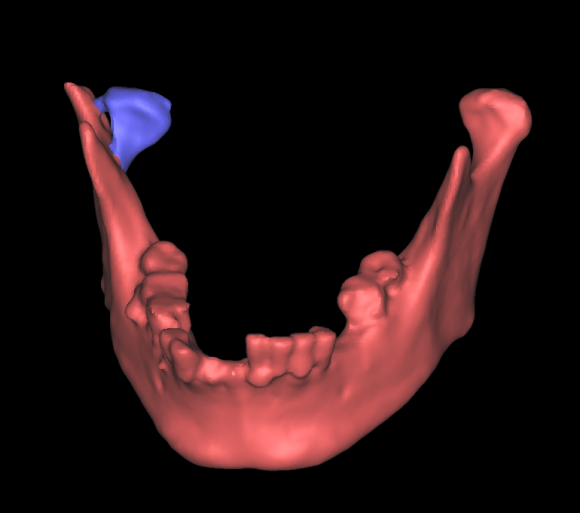

术后照片

老百姓口中的“下巴”,指的是面部下颌骨区域,医学专业上特指下颌骨前部中份的颏部。颏部因位置突出靠前,受伤瞬间人体反应等因素,容易造成直接损伤,形成软组织裂伤及下颌骨中间部分骨折。然而,由于下颌骨呈马蹄形结构,两侧向上借助升支形成的髁突与颅底结构形成颞下颌关节,如果颏部的直接外力过大,力量沿升支传导向上,就可能造成下颌骨髁突骨折。

髁突骨折较一般下颌骨骨折相对复杂。首先,髁突参与形成颞下颌关节,该关节是人体最灵活、功能最复杂的关节之一,一旦遭受损伤,可能出现咬合紊乱、张口受限、关节强直、关节炎等症状;由于髁突为生长发育中心,未成年人还可能影响颌面部的发育。其次,髁突骨折分类及相应治疗原则多样,根据骨折的部位可简易分成髁头、髁颈、髁基骨折,每种分类又根据移位等情况可分为不同亚型,不同分类亚型需正确选择手术适应症,才能达到最佳治疗效果。第三,髁突手术涉及支配面部表情肌的运动神经—面神经,分泌唾液的大腺体—腮腺等重要解剖结构,需熟练掌握手术技巧,以免出现面瘫等影响患者美观的并发症。